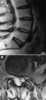

Extradural cyst

Tarlov cysts, are type II innervated meningeal cysts, cerebrospinal-fluid-filled (CSF) sacs most frequently located in the spinal canal of the S1-to-S5 region of the spinal cord (much less often in the cervical, thoracic or lumbar spine), and can be distinguished from other meningeal cysts by their nerve-fiber-filled walls. Tarlov cysts are defined as cysts formed within the nerve-root sheath at the dorsal root ganglion. [Source: Wikipedia ]